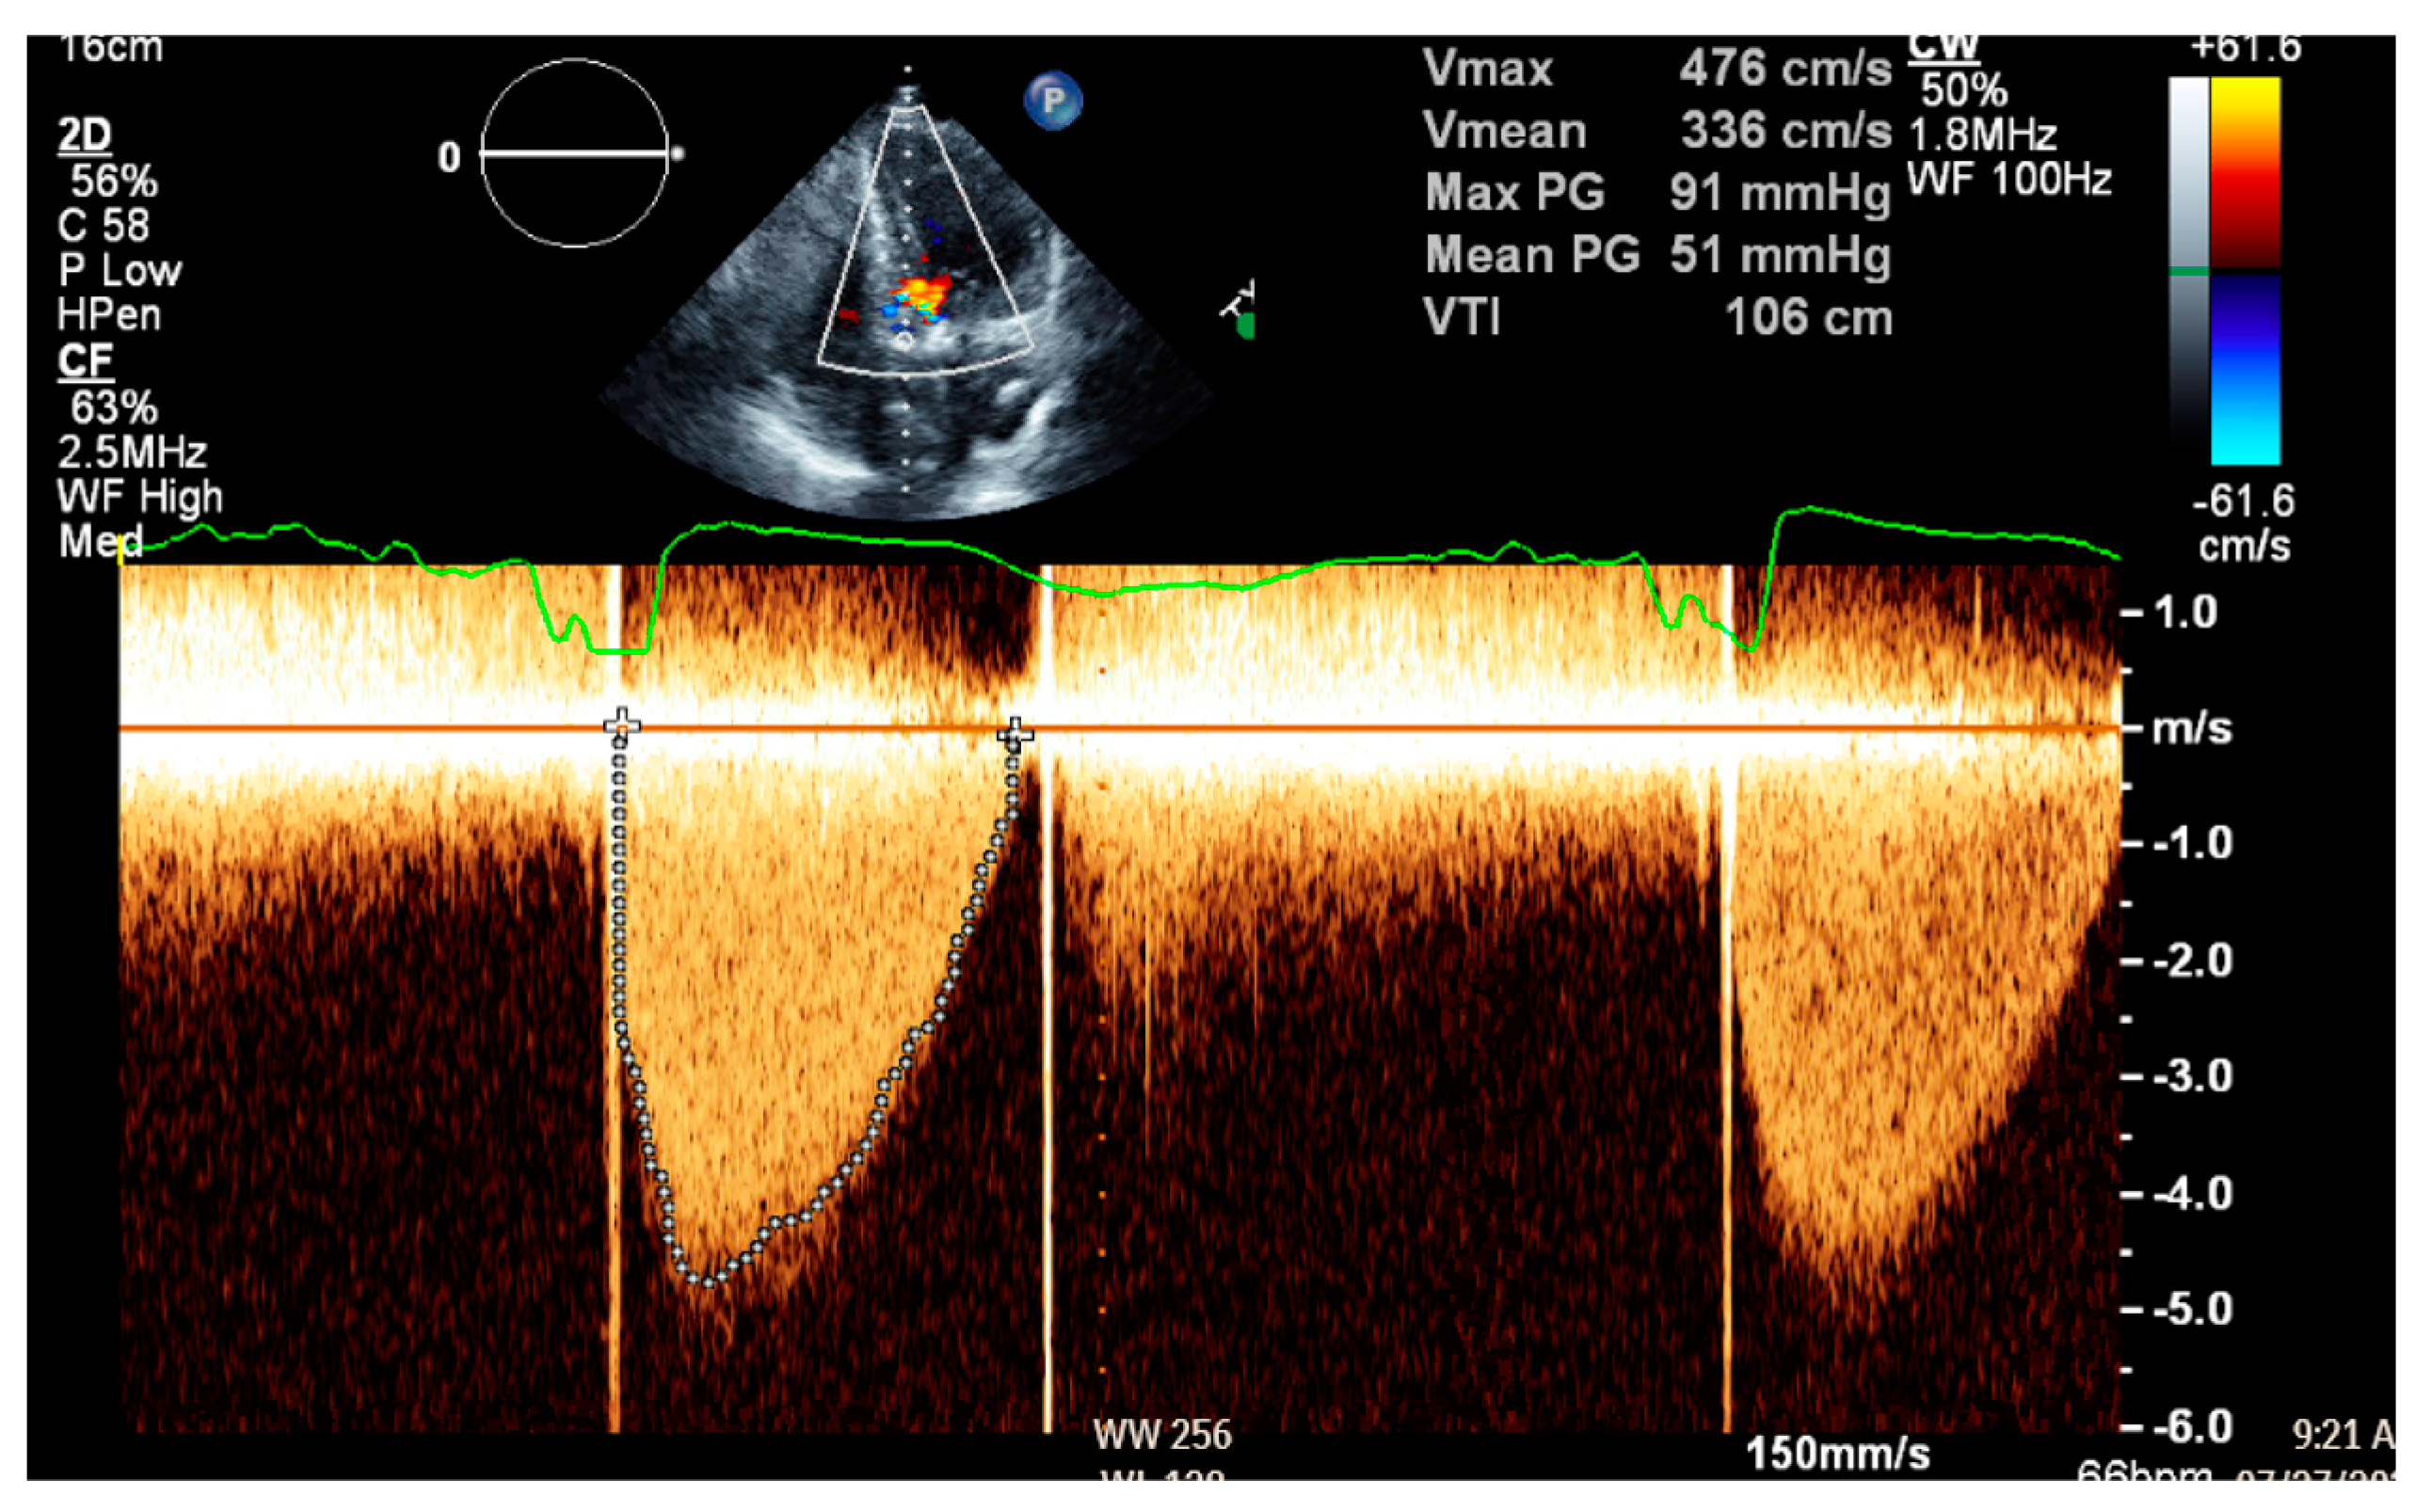

2. Patient Case